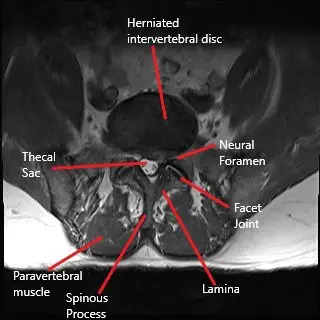

Back pain and radiculopathy may limit a patient’s physical intimacy, so much so they may cease their sexual activity. Microdiscectomy is a gold standard surgery to alleviate symptoms of lumbar radiculopathy due to herniated intervertebral disc. However, a symptom most commonly not discussed after the surgery is the resumption of sexual intimacy.

Healthy sex life is an essential predictor of a patient’s wellbeing. Back pain with radiculopathy due to herniated intervertebral disc commonly hampers a patient’s sex life. Pain during sexual activity as well as the anticipation of pain, both play in dissatisfaction during sex. Some patients may cease all sexual activity secondary to discomfort which may only add to the emotional aspect of radicular back pain.

Microdiscectomy surgery is a minimally invasive surgery performed with an operating microscope or an endoscope. The minimum invasive nature of the surgery leads to less cutting of the muscles and tissues while accessing the disc. The smaller incision also leads to less formation of fibrotic tissue after the surgery. The patients undergoing microdiscectomy are able to return to work and their day-to-day activities sooner than an open approach surgery.